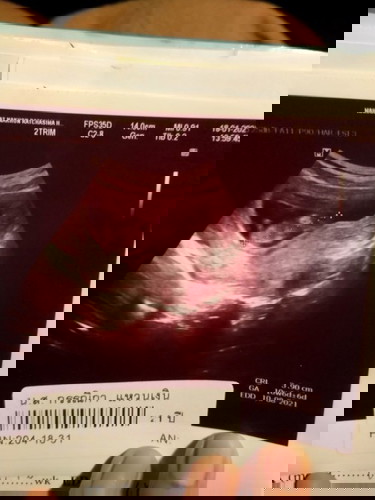

ในที่สุดก็มาให้เห็น

ดีใจมากค่ะ ยิ้มทั้งน้ำตาเลย คิดว่าแต่เป็นท้องลมซ่ะแล้ว

8วีคยังไม่เจอค่ะ มาเจอ10วีค เดี๋ยวน้องก็มานะคะ